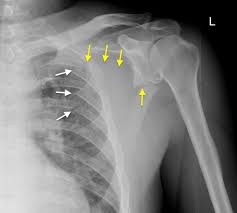

causes of shoulder dislocation

weakness of rotator cuff tendons and tendonitis, or trauma

head of humerus subluxes from glenoid cavity

usually when humerus is in abduction or flexion

occurs in the inferior direction and aspect

weakest region of capsule

humerus pulled either anterior/posterior to shoulder joint upon which rotator cuff muscles are injured

arm hangs limp at prominent “step deformity” space between acromion and humeral head

clavicle fracture